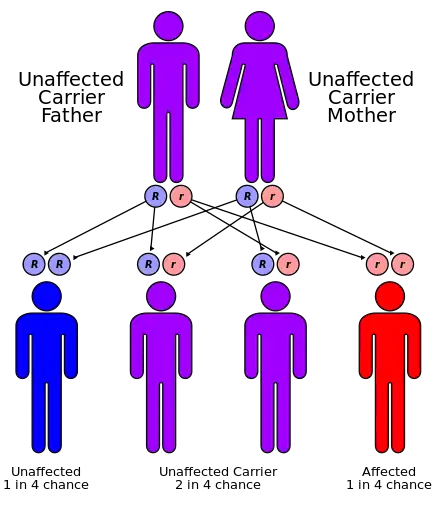

2-hydroxyglutaric aciduria is a rare neurometabolic disorder characterized by the significantly elevated levels of hydroxyglutaric acid in one's urine. It is either autosomal recessive or autosomal dominant.[1]

The cause of this condition are mutations in D2HGDH gene which encodes mitochondrial D-2-hydroxyglutarate dehydrogenase. The IDH2 gene has been found to be involved in this condition as well[3]

The D2 form is rare, with symptoms including macrocephaly, cardiomyopathy, mental retardation, hypotonia, and cortical blindness.[7] It is caused by recessive mutations in D2HGDH[8] (type I) or by dominant gain-of-function mutations in IDH2[9] (type II).

The combined form is characterized by severe early-onset epileptic encephalopathy and absence of developmental progress.[10] It is caused by recessive mutations in SLC25A1 encoding the mitochondrial citrate carrier.[11]